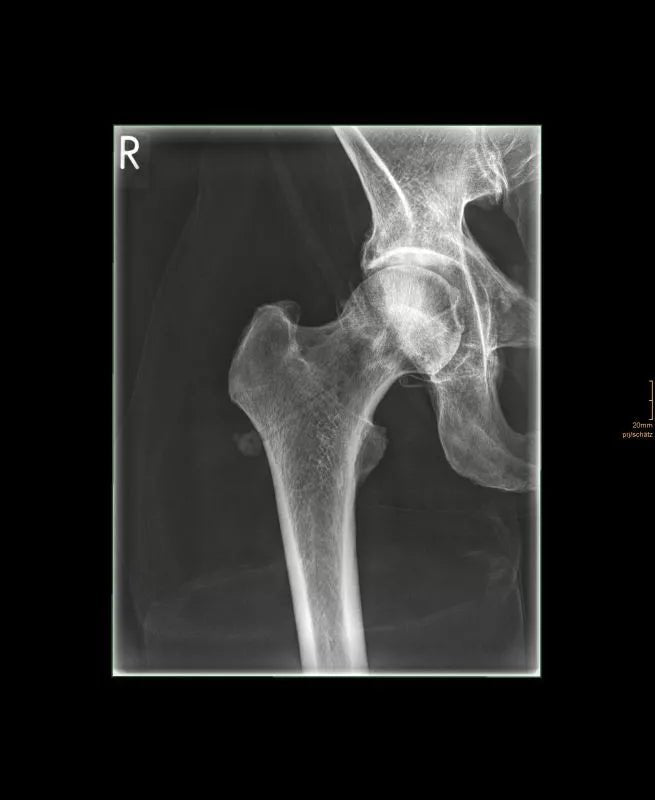

The whole-body X-ray phantom serves for practical training in projection radiography as well as in positioning and positioning techniques. It enables the production of realistic X-ray images under training conditions and depicts anatomical structures in their natural size.

The phantom contains a natural human skeleton. Additionally, the outlines of the larynx, lungs, heart, and kidneys are integrated, appearing as shadows on the X-ray images. This allows for the creation of images that accurately reflect the conditions found in patients. The use of a real skeleton enables the identification of bony landmarks that are not visible in plastic models.

The joints are mounted with full mobility, allowing positioning in common radiological standard positions, including special positions such as the frog position and pronation and supination of the forearm. The arms can be raised, so the phantom can also be used for bone examinations in CT scans. Particular attention was paid during assembly to the realistic representation of the joint spaces.

Each phantom is a handcrafted, unique piece. Variations in size, design, and appearance are possible. Depending on the model, pathological findings may be present. The revised design was developed in collaboration with a German training institution for medical-technical radiology assistants and meets the requirements of modern training concepts.